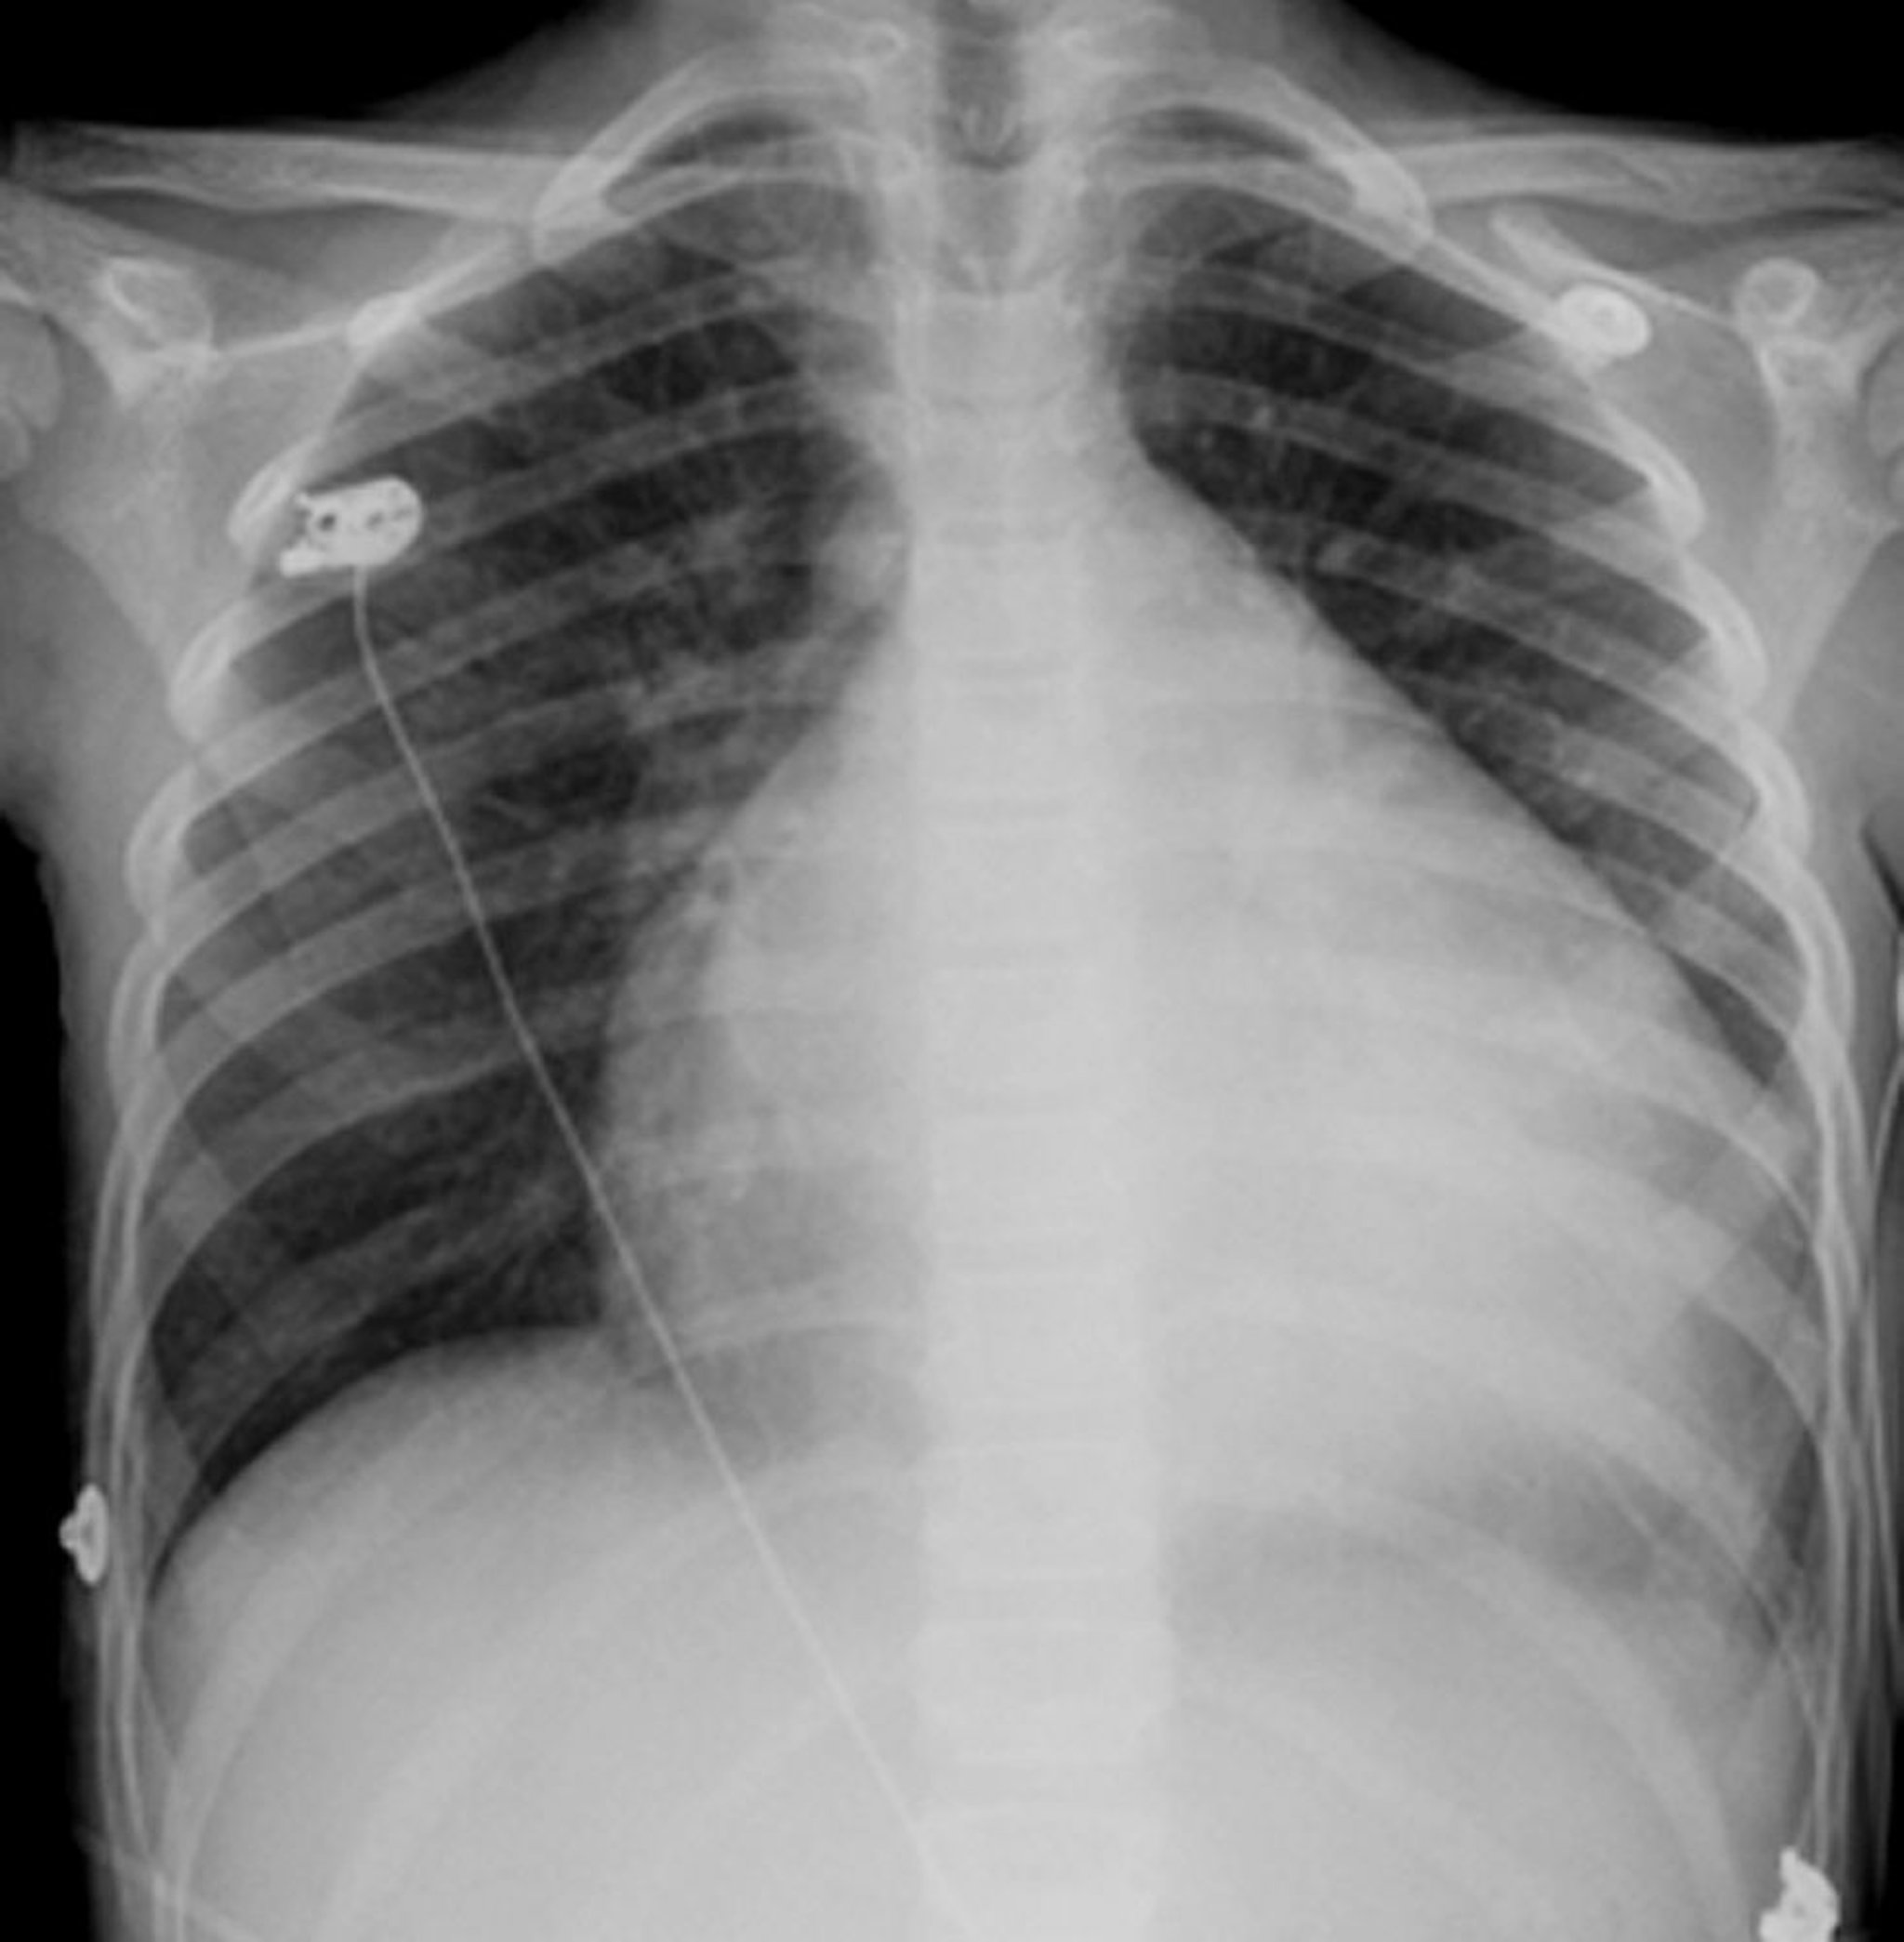

يبدو القلب كرويًا، بشكل بنية بيضاء في مركز الصدر.يشغل القلب عادةً مساحة أقل من مساحة نصف الصدر، ولكن عند هذا الشخص المُصاب بتضخم القلب فإن القلب يشغل حوالى ثلاثة أرباع مساحة الصدر.